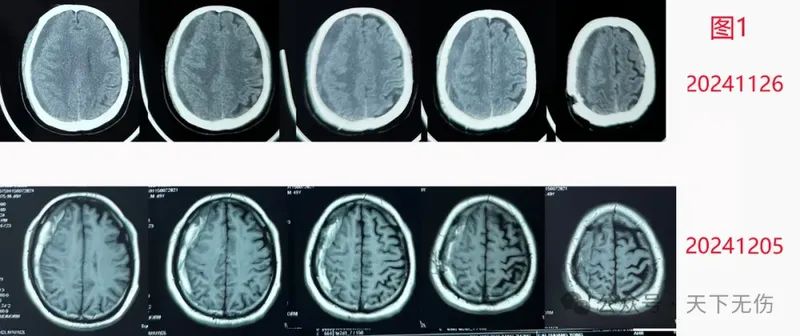

國(guó)各地求診于我的慢性硬膜下血腫患者數(shù)量在不斷增加,見(jiàn)過(guò)的患者多,各種情況就見(jiàn)得多,也因此遇到一些因應(yīng)用激素而導(dǎo)致患者疑慮、甚至自動(dòng)停藥,或者主管醫(yī)生拒絕用藥的情況;當(dāng)然更多的患者使用激素體驗(yàn)良好。L女士,69歲,是某著名醫(yī)院的著名專家,因摔傷頭部后被確診慢性硬膜下血腫。她不希望手術(shù)治療,來(lái)我門診治療。我看她的血腫量不太多,就開(kāi)具了他汀加激素治療方案。治療第1周的CT復(fù)查看到血腫沒(méi)有減少,反而略有增大。她坦白告訴我,她對(duì)激素有疑慮,沒(méi)有應(yīng)用。我為她做了解釋:我們用藥量很少,最多用4周,應(yīng)該不會(huì)對(duì)她造成永久性傷害。她聽(tīng)進(jìn)去我的解釋,開(kāi)始應(yīng)用激素,結(jié)果血腫越來(lái)越少(圖1)。2022年9月5日復(fù)查時(shí),血腫還沒(méi)有完全消失,但是她已經(jīng)正常上班。她抱怨吃激素后雙腳腫脹明顯,又覺(jué)得頭疼頭暈癥狀緩解,就自己停用了地塞米松。后來(lái)她沒(méi)有再回來(lái)復(fù)查過(guò),只是電話告知我,她已經(jīng)痊愈而且雙腳腫脹也已消除。H先生,43歲,因練習(xí)拳擊導(dǎo)致左顳部受傷后發(fā)展成慢性硬膜下血腫。他不想手術(shù),2024年10月24日輾轉(zhuǎn)從北京一家著名醫(yī)院來(lái)宣武找我門診。我給他開(kāi)具了他汀加激素藥物治療方案,叮囑他2周復(fù)查。他1周后就匆匆忙忙來(lái)復(fù)查。我看他的血腫較10月24日不僅沒(méi)有縮小,還疑似增加了,伴隨頭疼癥狀加重。問(wèn)診后才得知,他這一周主要是服用了阿托伐他汀鈣,沒(méi)有應(yīng)用激素。原因是他在口服地塞米松后不到一小時(shí),就渾身顫抖、心率加快,于是自停藥。我看他精神焦慮、頭疼明顯,就安排他住院接受手術(shù)治療。結(jié)果他非常害怕,并沒(méi)有去住院,反而是回到家中,重新?lián)炱鹞业乃〖拥厝姿煞桨福撕蟮拿看螐?fù)查,他的血腫都在減少,直到今年1月16日再次復(fù)查,確診他已經(jīng)治愈(圖2)。F先生,82歲,是某市知名糖尿病專家,他自己是糖尿病患者。他因外傷導(dǎo)致左側(cè)硬膜下血腫。老先生完全清醒,左下肢有些力弱(剛開(kāi)始我也納悶,左側(cè)血腫應(yīng)導(dǎo)致右下肢無(wú)力,為什么是左下肢無(wú)力?)。他的主管醫(yī)生征詢我意見(jiàn)后,我臨時(shí)加大了地塞米松的量。剛開(kāi)始,我還擔(dān)心老教授不愿意接受我主張的激素治療,畢竟它會(huì)干擾血糖血壓。但老教授告訴我,他搞了一輩子糖尿病,對(duì)激素的副作用完全知曉,而且自己可以調(diào)節(jié)血糖到基本正常,愿意接受我的他汀加激素治療方案。后續(xù)復(fù)查,眼見(jiàn)他的血腫逐步減少(圖3),左下肢力量也逐步增強(qiáng),我正期待他的最新復(fù)查結(jié)果。L女士,39歲,因頭部外傷導(dǎo)致左側(cè)慢性硬膜下血腫,于今年3月6日接受鉆孔引流術(shù),手術(shù)成功。她術(shù)前就有視力障礙,術(shù)后發(fā)現(xiàn)雙眼視力進(jìn)一步下降,已經(jīng)到了幾乎失眠的地步。她兩口子從外地跑到北京某著名眼科??漆t(yī)院診療,確診顱內(nèi)壓增高(400mmH2O),雙側(cè)視乳頭水腫,術(shù)后仍殘余硬膜下血腫。該眼科醫(yī)生推薦患者來(lái)找我,結(jié)果她在我診室內(nèi),就因顱內(nèi)壓增高而惡心嘔吐。我果斷收她入院,先排除顱內(nèi)靜脈竇血栓,給予激素消除視乳頭水腫,給予高滲鹽水降低顱內(nèi)壓,給予他汀消除殘余血腫。她的癥狀迅速減輕,并且告訴我,當(dāng)輸上激素時(shí),她自覺(jué)有一股清冽之氣從輸液的胳膊進(jìn)去,進(jìn)入顱內(nèi),眼睛就亮了。她是3月21日來(lái)北京那家醫(yī)院看病的,但找我看病用藥已經(jīng)是3月26日,3月29日復(fù)查CT已可見(jiàn)硬膜下血腫縮小,與癥狀消減完全符合,且僅僅治療3天(圖4)。再過(guò)2天,她的顱內(nèi)壓也降到了130mmH2O。我知道這種患者的視力恢復(fù),決定性的是正確而及時(shí)的康復(fù),她一定還會(huì)進(jìn)步。我果斷要求她出院去接受高壓氧治療聯(lián)合鼠神經(jīng)生長(zhǎng)因子注射。昨天患者出院了,她的頭痛、惡心嘔吐緩解了,視力也已部分恢復(fù)。Y老先生,96歲,是我國(guó)某醫(yī)學(xué)專業(yè)領(lǐng)域的泰斗級(jí)教授。他因?yàn)檩p微外傷發(fā)生左側(cè)硬膜下血腫,他的右手已經(jīng)不能持筷,也不能下地行走了。我建議他采用小劑量短療程激素配合阿托伐他汀鈣治療,但他有嚴(yán)重糖尿病,他的主治醫(yī)生不敢完全采納我的激素治療方案,也因此他的癥狀也就沒(méi)有緩解。我主動(dòng)聯(lián)系這位主治醫(yī)生,跟他解釋為什要用激素,他很快聽(tīng)取我的意見(jiàn),加上了小劑量激素。今天距離我會(huì)診這位前輩已是過(guò)去8天,也是他加上激素治療后的第3天。電話隨訪這位主治醫(yī)生獲悉,接受他汀加激素治療方案后,老主任的血糖一度突然升高到19mmol/L,讓所有關(guān)心主任的醫(yī)生都擔(dān)心了。這位主治醫(yī)師隨后將地塞米松改成更小劑量。今天證實(shí),老主任各方面機(jī)能、包括右手肌力已明顯緩解。我期待著一周后老主任的檢查結(jié)果給我一個(gè)驚喜。。地塞米松是1948年由美國(guó)科學(xué)家菲利普·肖瓦爾特·亨奇(PhilipShowalterHench)和愛(ài)德華·卡爾文·肯德?tīng)枺‥dwardCalvinKendall)成功從腎上腺皮質(zhì)中分離得到,并發(fā)現(xiàn)其具有顯著的抗炎作用,1950年獲得諾貝爾生理學(xué)或醫(yī)學(xué)獎(jiǎng)。1960年代,地塞米松被批準(zhǔn)用于治療多種炎癥和免疫相關(guān)疾病,地塞米松能有效減輕腦腫瘤或腦外傷引起的腦水腫,因此神經(jīng)外科常應(yīng)用它來(lái)自治療腦水腫;在腫瘤領(lǐng)域,則被用于治療化療或放療后并發(fā)癥。我國(guó)非典流行期間和COVID-19疫情中,曾廣泛應(yīng)用地塞米松治療感染患者;而英國(guó)學(xué)者報(bào)道,地塞米松可使重癥COVID-19患者的死亡率降低約1/3。地塞米松最為令人擔(dān)憂的副作用是股骨頭壞死。有統(tǒng)計(jì)認(rèn)為,長(zhǎng)期使用較大劑量的糖皮質(zhì)激素患者中,股骨頭壞死的發(fā)生率約為3%~34%。如果應(yīng)用地塞米松的劑量超過(guò)每天3mg,長(zhǎng)期使用的話,股骨頭壞死的發(fā)生率可達(dá)5%-25%。地塞米松治療慢性硬膜下血腫始于1960年代加拿大醫(yī)生的發(fā)明,而且迄今在北歐、北美還被廣泛用來(lái)預(yù)防或者治療慢性硬膜下血腫術(shù)后復(fù)發(fā)。2020年劍橋大學(xué)團(tuán)隊(duì)發(fā)表臨床研究結(jié)果認(rèn)為地塞米松相比于安慰劑沒(méi)有促進(jìn)慢性硬膜下血腫吸收,且地塞米松應(yīng)用后死亡率較對(duì)照組高,但是,劍橋團(tuán)隊(duì)在19天內(nèi)應(yīng)用地塞米松的總劑量達(dá)到了110.5mg。我認(rèn)為,激素治療慢性硬膜下血腫歷史久遠(yuǎn),且今天歐美醫(yī)生還在應(yīng)用,該方案具有生命力。雖然其副作用讓人生畏,但降低劑量則可能避免或減輕,因此,我提出了以阿托伐他汀鈣為主、以小劑量地塞米松為輔的阿托伐他汀鈣聯(lián)合地塞米松治療慢性硬膜下血腫新方案,4周的地塞米松總劑量最多是49mg,不及劍橋團(tuán)隊(duì)報(bào)道的地塞米松劑量的一半。我從2009年開(kāi)始他汀為基礎(chǔ)的藥物治療慢性硬膜下血腫研究,治療的患者數(shù)量已經(jīng)超過(guò)1400余例,而從2014年開(kāi)始的地塞米松與阿托伐他汀鈣聯(lián)合方案治療慢性硬膜下血腫患者,其數(shù)量已近千例,但僅有1例患者發(fā)生疑似發(fā)生地塞米松相關(guān)股骨頭壞死。這位患者僅接受過(guò)4周的他汀加地塞米松藥物治療,治療期間無(wú)并發(fā)癥。3年后隨訪發(fā)現(xiàn)他罹患右側(cè)股骨頭壞死,是否跟激素有關(guān)?我至今不敢確認(rèn)。我特別理解醫(yī)生和患者對(duì)地塞米松應(yīng)用的顧慮,地塞米松除了可能誘導(dǎo)股骨頭壞死,還可能擾亂血糖代謝、心率和血壓,但是,地塞米松藥物相關(guān)副作用均與劑量和療程密切相關(guān),我們的實(shí)踐證明,我們的短期、小劑量應(yīng)用方案對(duì)于絕大多數(shù)慢性硬膜下血腫患者是可靠、有效和安全的,而且多數(shù)患者加上激素療效良好。我會(huì)繼續(xù)應(yīng)用該方案治療慢性硬膜下血腫患者,但也會(huì)更加關(guān)注其安全性專家介紹江榮才教授?首都醫(yī)科大學(xué)宣武醫(yī)院神經(jīng)外科二級(jí)教授,主任醫(yī)師,博導(dǎo)?首都醫(yī)科大學(xué)宣武醫(yī)院神經(jīng)外科神經(jīng)外科副主任兼任危重癥中心主任?中華醫(yī)學(xué)會(huì)神經(jīng)外科學(xué)分會(huì)委員、腦外傷學(xué)組副組長(zhǎng)?中國(guó)醫(yī)師協(xié)會(huì)神經(jīng)外科醫(yī)師協(xié)會(huì)神經(jīng)重癥專委會(huì)副主任委員?國(guó)家創(chuàng)傷醫(yī)學(xué)中心顱腦創(chuàng)傷專業(yè)委員會(huì)副主任委員?中國(guó)老年保健協(xié)會(huì)神經(jīng)外科學(xué)創(chuàng)新與轉(zhuǎn)化分會(huì)首任會(huì)長(zhǎng)?擅長(zhǎng)復(fù)雜重型腦外傷、腦出血及慢性硬膜下血腫的診療。?是他汀治療硬膜下血腫的主要發(fā)明者,治療慢性硬膜下血腫患者超1400名,總治愈率約90%?!境鲈\時(shí)間】每周四下午(神經(jīng)外科專家門診)每周三上午(神經(jīng)外科特需門診)